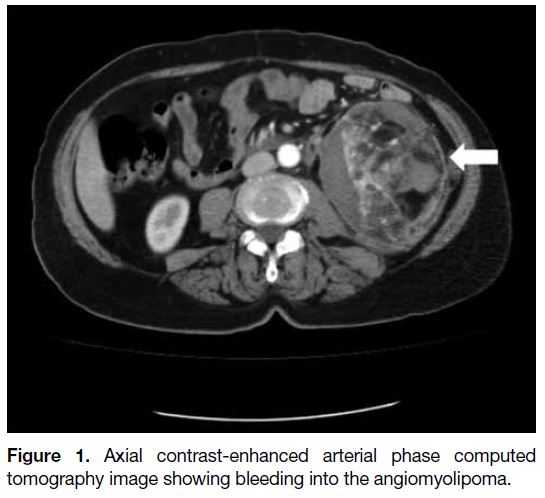

Two of the space-occupying lesions on CT (28.6%)

were AMLs (Figure 1), one (14.3%) was a haemorrhagic cyst in a patient with adult polycystic kidney disease

(APCKD), and four (57.1%) were solid mass lesions. The

Figure 1. Axial contrast-enhanced arterial phase computed tomography image showing bleeding into the angiomyolipoma